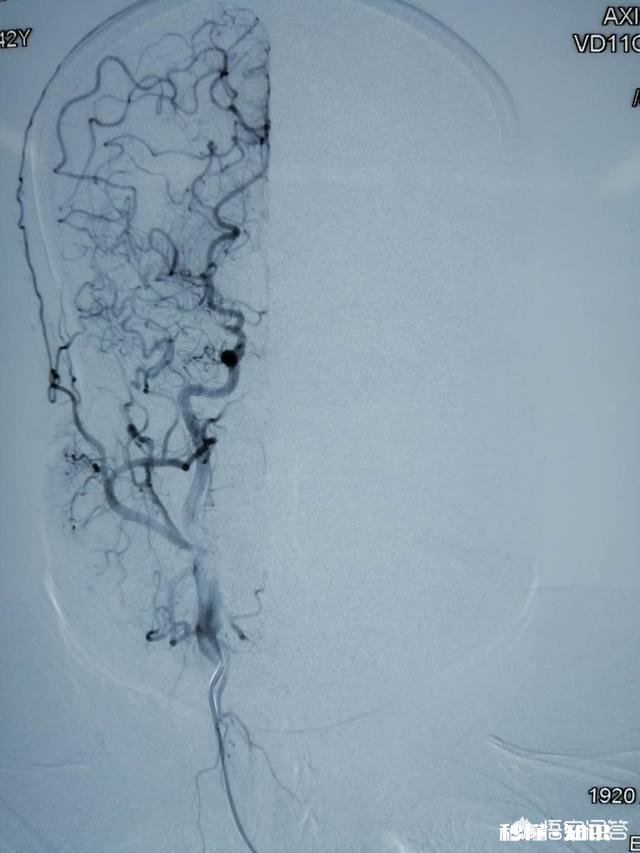

烟雾病主要是大脑动脉(比如颈内动脉末端、大脑前动脉、大脑中动脉,有时也包括大脑后动脉)狭窄或闭塞,继而导致颅底异常的代偿小血管网形成,在脑血管造影时呈现密集成堆的小血管影,故名烟雾病 。

什么是烟雾病烟雾病,又称moyamoya?。钤缡侨毡狙д咛岢龅模侵奕朔⒉〗隙?。烟雾病指的是在脑底出现的异常血管网,具体指Wills环双侧主要分支血管发生的一种慢性进行性的闭塞或者狭窄,可以激发侧支异常小血管网,在进行脑血管造影时可见密集成堆的烟雾状小血管影,故称为烟雾病 。